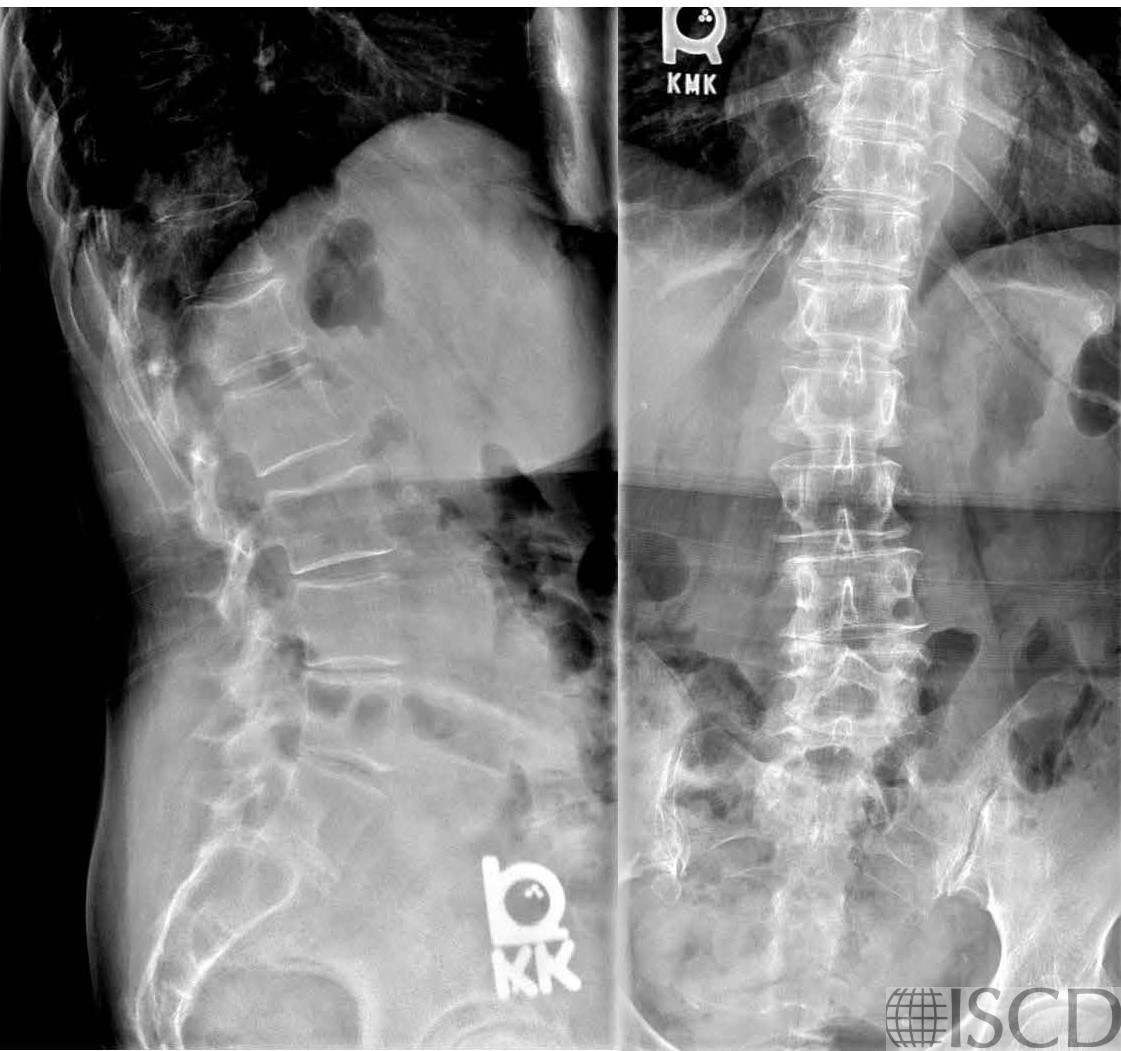

The Hologic lumbar spine DXA scan shows 6 lumbar vertebral bodies.

The corresponding radiographic was read as “six nonrib-bearing lumbar vertebrae are seen with lumbarization of S1”.